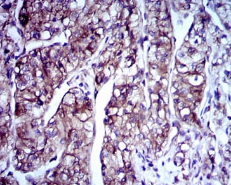

IHC    1/200 - 1/1000